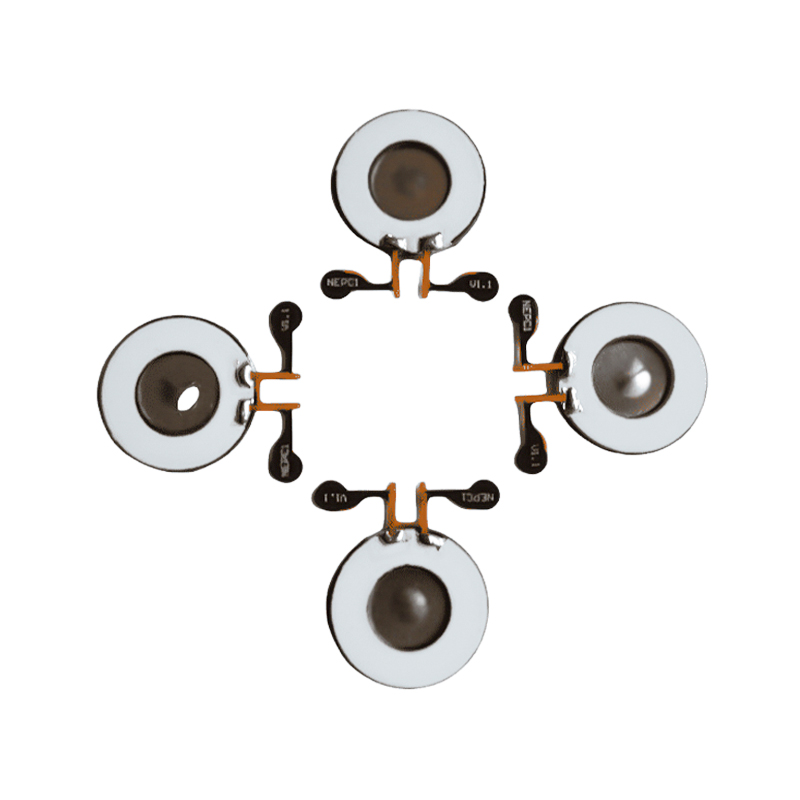

Bezolovnatá piezoelektrická keramika je známá jako piezoelektrická průmyslová „perla“, v budoucnu postupně ve všech aspektech nahradí piezoelektrickou keramiku na bázi olova, která již má stejný piezoelektrický výkon, a piezoelektrický plech na bázi olova. Je zcela netoxický, nezávadný, bezpečný a šetrný k životnímu prostředí, neobsahuje olovo, antimon a další těžké kovy a další prvky s omezením Rohs, vysoká Curieova teplota Tc-328°C, velmi nízká elektrická ztráta TangentLoss Bezolovnatý piezoelektrický lékařský atomizační čip má proto velkou komerční hodnotu a univerzální hodnotu, skutečně netoxická a ekologická, bezolovnatá piezoelektrická keramika kromě neznečišťujících, piezoelektrických výkonů srovnatelných s keramikou na bázi olova, se stane oblíbenou piezoelektrickou keramikou šetrnou k životnímu prostředí. Po letech výzkumu a vývoje, po neustálém testování a experimentování, se společnosti podařilo vyrobit bezolovnatý lékařský atomizační čip tak, aby dosáhl stejného množství atomizace jako atomizační čip na bázi olova a stejných požadavků na průměr částic. Bezolovnatý lékařský nebulizační čip Mesh bude jistě zářit a získá širokou škálu scénářů použití.

Ultrazvukové kosmetické destičky a měniče jsou vyrobeny z piezoelektrické keramiky. Princip jejich činnosti je založen na piezoelektrickém jevu, kdy ultrazvukové vlny vznikají přivedením napětí, které způsobí, že materiál vibruje. Ultrazvukové měniče jsou navrženy s přesností a materiály jsou pečlivě vybírány, aby bylo zajištěno, že jsou schopny vyzařovat ultrazvukové vlny o specifických frekvencích a intenzitách, aby vyhovovaly potřebám různých aplikací. Ultrazvukové měniče mají navíc dobrou odolnost a spolehlivost a mohou si udržet stabilní výkon po dlouhou dobu. Díky vysoké citlivosti a stabilitě dokáže rychle reagovat na akustické signály v různých médiích. Je vyrobena z vysoce kvalitních materiálů s dobrou odolností proti oděru a korozi, zajišťující stabilní práci po dlouhou dobu. Kromě toho má plátek ultrazvukového měniče kompaktní design a snadno se instaluje a udržuje. Může být široce používán při ultrazvukovém čištění, ultrazvukovém svařování, ultrazvukovém měření atd., čímž poskytuje efektivní a spolehlivá řešení konverze akustických vln pro různé průmyslové aplikace. Piezoelektrická keramika jsou funkční materiály, které dokážou přeměnit mechanickou a elektrickou energii na sebe. Když jsou vystaveny mechanickému tlaku, generují elektrický náboj, jev známý jako pozitivní piezoelektrický efekt; naopak, když je aplikováno elektrické pole, deformují se, což je jev známý jako inverzní piezoelektrický jev. Piezoelektrická keramika je široce používána v senzorech, akčních členech, ultrazvukových generátorech, kombajnech energie a dalších oborech. Například senzory mohou detekovat malé změny tlaku a převést je na elektrické signály; akční členy mohou převádět elektrické signály na přesné mechanické pohyby. Díky svým jedinečným fyzikálním vlastnostem hraje piezoelektrická keramika důležitou roli v přesném řízení a vysoce přesných měřicích zařízeních. Ultrazvuková piezoelektrická keramika má vysokou citlivost a stabilitu a dokáže účinně převádět elektrickou energii na akustickou a kinetickou energii, což je široce používáno v lékařském zobrazování, nedestruktivním testování, měření vzdálenosti a dalších oborech.

Ultrazvukový atomizér je zařízení, které využívá principu ultrazvukové vibrace (přeměny energie) k přeměně kapaliny na drobné kapičky. Pracovní princip spočívá v jedinečných piezoelektrických vlastnostech piezoelektrické keramiky, atomizační kus při příjmu odpovídající buzení signálu elektrického pole, bude produkovat odpovídající oscilační frekvenci, prostřednictvím role vysokofrekvenční vibrace kapalné kavitace odhozené z povrchu vody, aby se vytvořil druh částic vodní mlhy, atomizovaný velkým počtem záporných iontů a malých částic molekul, dosáhnout zvýšení okolní vlhkosti, role čerstvého vzduchu. Povrch atomizéru je potažen skelným smaltem při vysoké teplotě 800 stupňů pro ochranu stříbrných elektrod piezoelektrického plechu, zvýšení odolnosti atomizéru vůči kyselinám a zásadám a oxidaci a zvýšení životnosti atomizéru. Široce se používá ve vnitřních zvlhčovačích, čističkách vzduchu, ošetření lékařských rozprašovačů a kosmetických automobilech, e a dalších oblastech, ale také vhodné pro sklady, továrny, zvlhčování, dezinfekci, k vytvoření atmosféry zvlhčovacího zařízení. Zamlžovací tablety se používají hlavně při průmyslovém zvlhčování, lékařském zamlžování, aromaterapeutickém zamlžování, zvlhčování prostředí, zamlžování zahrady a dalších scénách.